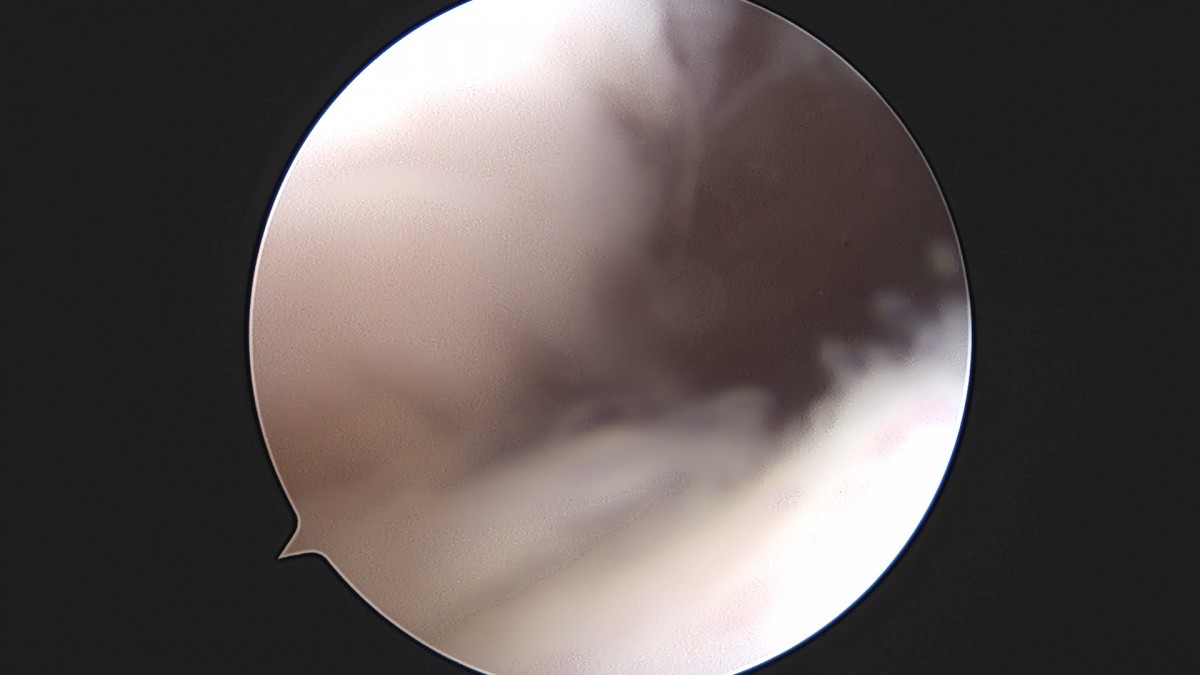

이재상원장님 무릎 반월상 연골판 절제술 최용O 환자

작성자 최고관리자 댓글 0건 조회 379회 작성일 25-09-16 15:57